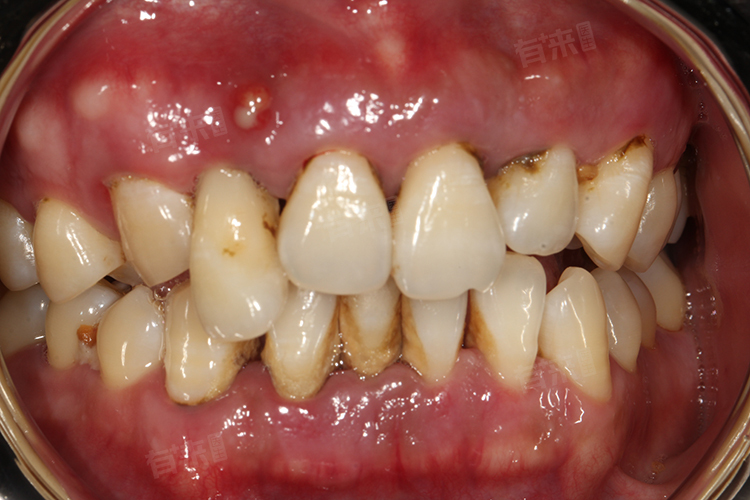

3、牙结石:牙结石是牙齿表面钙化的牙菌斑及其他沉积物,常呈现黑色或深褐色。牙结石不仅影响美观,还容易吸附细菌,引发牙周炎症。若不及时处理,可能导致牙周疾病,影响牙齿稳固性。

2、饮食因素:经常饮用深色饮料,如可乐、咖啡、茶等,也会导致牙齿表面出现黑色污垢。这些饮料中的色素颗粒容易吸附在牙齿表面及邻面,形成褐色或黑色的斑片,食物残渣在口腔中长时间停留,也会与口腔中的细菌作用,产生酸性物质,腐蚀牙齿,形成龋洞,进而在龋洞内积累食物残渣和细菌,形成黑色外观。

5、牙齿发育不良:先天性牙齿发育不良,如釉质钙化不全,会导致牙釉质层粗糙,容易吸附食物中的色素和细菌,形成黑色污垢。这种情况多与遗传因素或孕期营养不足有关。